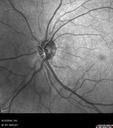

52 year old HIV negative man. May of 2014 the right eye had a vitrectomy for a floater. He was told that the doctor couldn't get all the floaters. He had cataract surgery (required 2 surgeries for the cataract). Them a different retina docotor then did another vitrectomy and scraped the scar tissue off the retina which had formed because the initial doctor couldn't get everything. The patient gave up a few months ago. He cannot see out of the right eye. There is constant flickering and distorted vision in the right eye. Since he stopped treatment his vision is no worse. He sees a fog out of the right eye and light and dark. 6/12/14 no pucker. The retina specialist who did the second vitrectomy also did laser to the macula to try to get rid of some of the swelling. The left eye is fine. The vision in the right eye is 20/63. There is diffuse chorioretinitis. There are no vitreous cells. With treatment of his neurosyphillis his vision improved from 20/63 to 20/32.

Syphilitic Chorioretinitis627 viewsSevere outer retinal atrophy and RPE non-geographic atrophy from syphilis. Vision improved from 20/63 to 20/32 with therapy. Images look a lot like DUSN. Patient had several surgeries (vitrectomy for floaters, vitrectomy for macular pucker, Avastin injections and macular laser for edema) prior by other retina specialists prior to being correctly diagnosed and treated.     (0 votes)